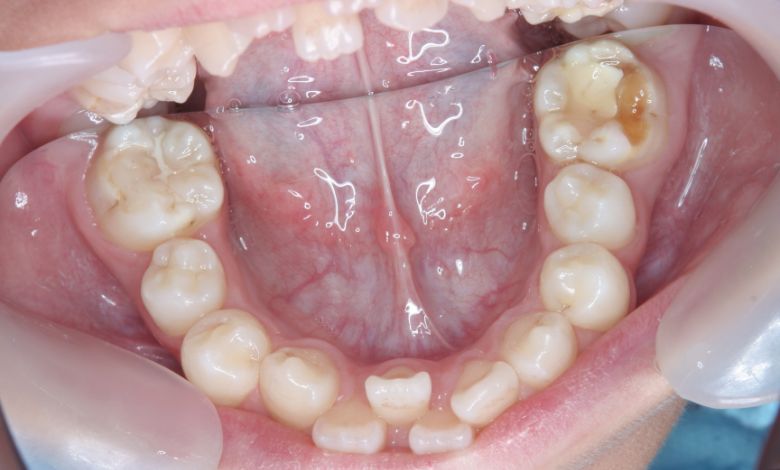

上下顎ともに犬歯が唇側に大きく突出しており、歯列弓が狭小なため、

他院では上下左右4本の便宜抜歯を前提とした矯正治療を提案されていました。

上顎には左右の犬歯が著しく唇側に偏位している

精密検査の結果、当院では抜歯を行わず、歯列弓の拡大によってスペースを確保し、非抜歯での矯正治療を選択しました。歯列の叢生(ガタガタ)は解消され、機能的かつ審美的に優れた咬合が得られました。